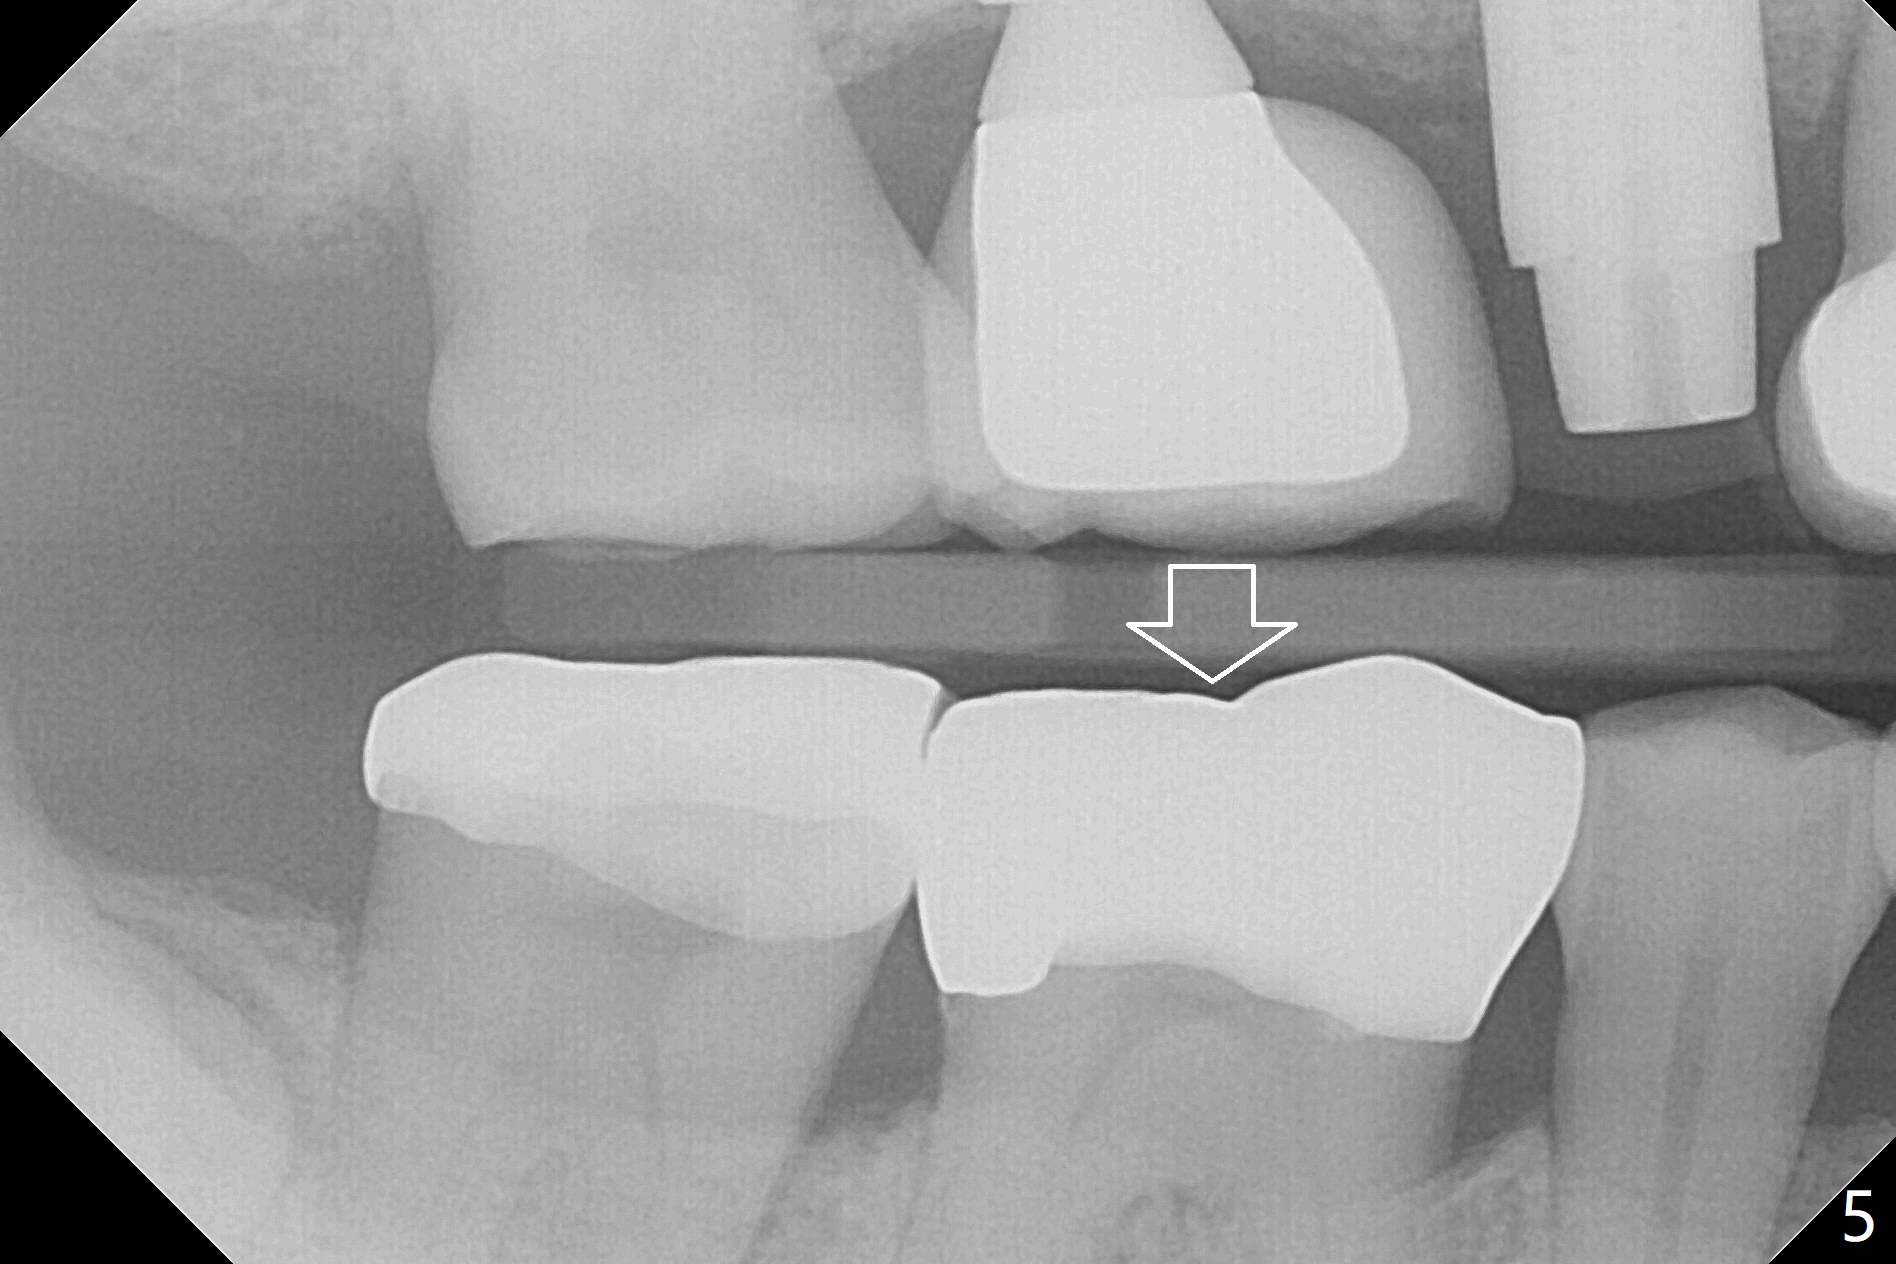

A 53-year-old man returns for #30 crown redo with distal open margin (Fig.1-3 arrowhead) after #4 implant. In addition to the distal margin caries, there is buccal one after removal of the existing crown. Composite build up is done for the buccal cavitation, whereas heavy chamfer margin is prepared distal. BW is taken immediately before cementation with open margin (Fig.4 ^). The latter disappears when the crown is cemented with pressure (Fig.5 arrow).